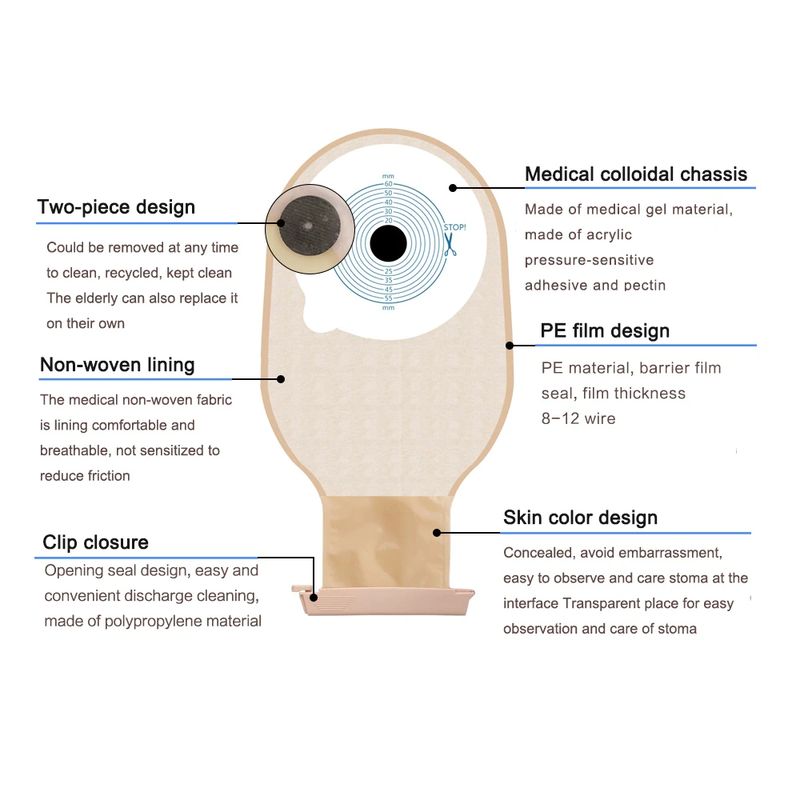

10 Uds. Bolsas de ostomía de sistema de una pieza bolsa de colostomía drenable estoma de ostomía 60mm Tamaño de corte Beige cubierta bolsa de orina con cierre de Clip

Descripción del producto La bolsa de cuidado de ostomía combina la barrera de la piel y la bolsa de colección en un sistema simple y fácil de administrar, proporcionando una gran simplicidad. La bolsa de colostomía es fácil de aplicar con el cierre de Velcro adjunto, proporcionando seguridad, ya que los sujetadores de plástico se bloquean en su lugar, fáciles de vaciar y irrigar. El propósito de reemplazar la ostomía 1. Observa la mucosa del estoma, las suturas circundantes y la piel circundante. 2. Limpia la piel alrededor del estoma, reduce el olor y aumenta la comodidad. 3. Evita que el agua fecal contamine la incisión abdominal a través de la fuga del chasis. 4. Si hay impregnación, asegúrese de reemplazarla a tiempo. Se recomienda cambiar el tiempo de 3-5 días para garantizar una respiración efectiva de la piel. Sentido común de la vida ostomía 1. Comer uniformemente, beber mucha agua y comer más verduras y frutas. 2. Evite comer demasiado rápido y tragar aire, masticar alimentos lentamente, Evite hablar mientras come, evite comer demasiado de una vez. 3. Evite las comidas con alto contenido de fibra y evite el bloqueo del estoma. 4. La ropa es suave y cómoda. 5. Evita el trabajo para aumentar la presión abdominal (como extraer objetos pesados). 6. Mantenga su estado de ánimo feliz. Paquete 10 unids/caja bolsa de ostomía